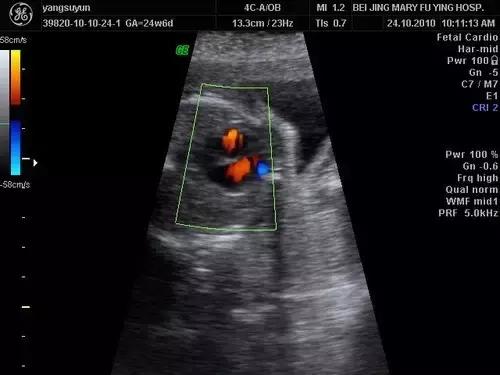

以前B超检查受机器和技术因素影响,胎儿心室强光点根本不可能看到,现在医院B超机器都先进了,技术也提高了,以前看不到的,现在能看到了,结果发出的报告却让孕妈非常担心,其实胎儿心室内点状强回声是一个声像图表现,而不是一种心脏畸形,更不是胎儿心脏异常诊断。中期妊娠声像图上可见到胎儿心室强光点的发生率为2.1-5%。

胎儿心室内点状强回声是如何发生的,目前原因还不是很清楚,专家们认为,可能是胎儿心室内腱索增厚形成的强回声反射,乳头中央矿物沉淀等,相信随着医学的进步会清楚地了解到发生机制的。

一般来说,胎儿左心室点状强回声的几率明显多于右心室,也可以同时出现,大部分强回声会随着孕周增加而缩小,回声强度也逐渐减弱,到足月妊娠时几乎完全消失,极少数可一直存在,直至分娩,甚至产后超声仍能观察到,对于大部分胎儿而言,心室内点状强回声可能无重要的临床意义,单纯光点小于5mm,一般是钙化现象,可以说这个光点基本上99%是没有问题的,孕妈们不用担心,其实这个光点不是胎儿心脏病,和胎儿心脏病没有什么关系。